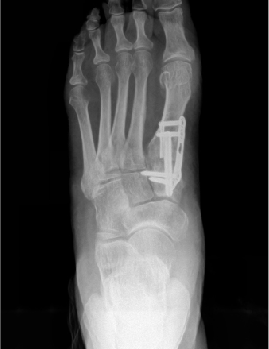

Therefore, most surgeons use common radiographic signs to rule out primary delay and eventual non-union. Some of these signs include the presence of a bridging callus, three of four cortices being bridged by callus formation and the resorption of fracture lines.2 Evaluation of the hardware across the proposed fusion site is also a good indicator. Hardware failure often indicates motion across the site with a lack of bony union, which places more force on the hardware, resulting in failure. Radiographic assessment is limited to the rate at which bony changes are visible in radiographs, which can take months.

Conversely, surgeons should also attend to the factors they can control. Ensure a stable rigid construct; augmentation of osteogenic, osteoinductive or osteoconductive properties; and establishment and maintenance of a normal anatomic alignment when possible. With the development of more anatomic contouring for internal and more “user-friendly” external devices, there are a variety of options available to choose from when determining how to obtain stable and rigid alignment. A combination of both plates and screws is often indicated to prevent any micromotion across the fusion site.